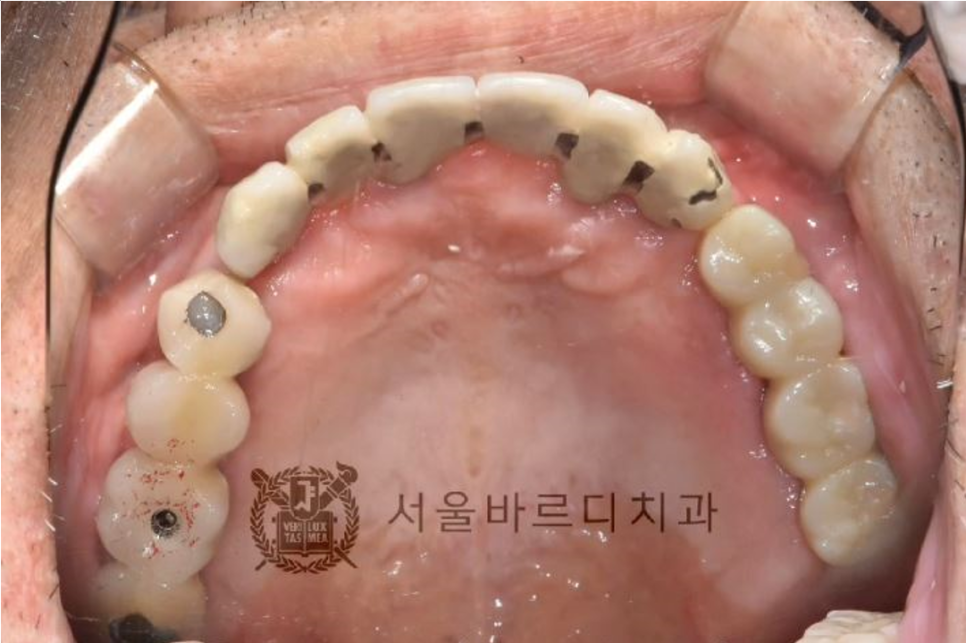

뼈와 임플란트가 잘 붙었으면

이제 보철물을 제작합니다.

저희 고덕치과는 스캐너 장비를 활용하여 컴퓨터 상에 정보를 담고

해당정보를 전송하여 보철물(크라운)을

제작하는 첨단 기술이 사용하고 있습니다.

이 방법은 오차 가능성을 줄여

좀더 편한 보철물을 제작하는 디지털 방식입니다.

20231107

기존 보철물보다 임플란트 한 개를 더 추가하여

총 4개의 치아를 회복시켜드렸습니다.

임플란트는 뿌리 부분이 가늘고 머리가 크기 때문에

힘을 더 잘 받기 위해 4개의 치아를 묶어서 제작하였습니다.

4개의 치아를 묶어드려야 더 튼튼하고

음식물도 끼지 않기 때문에

최대한 오래 오래 쓰실 수 있는 방법이었습니다.